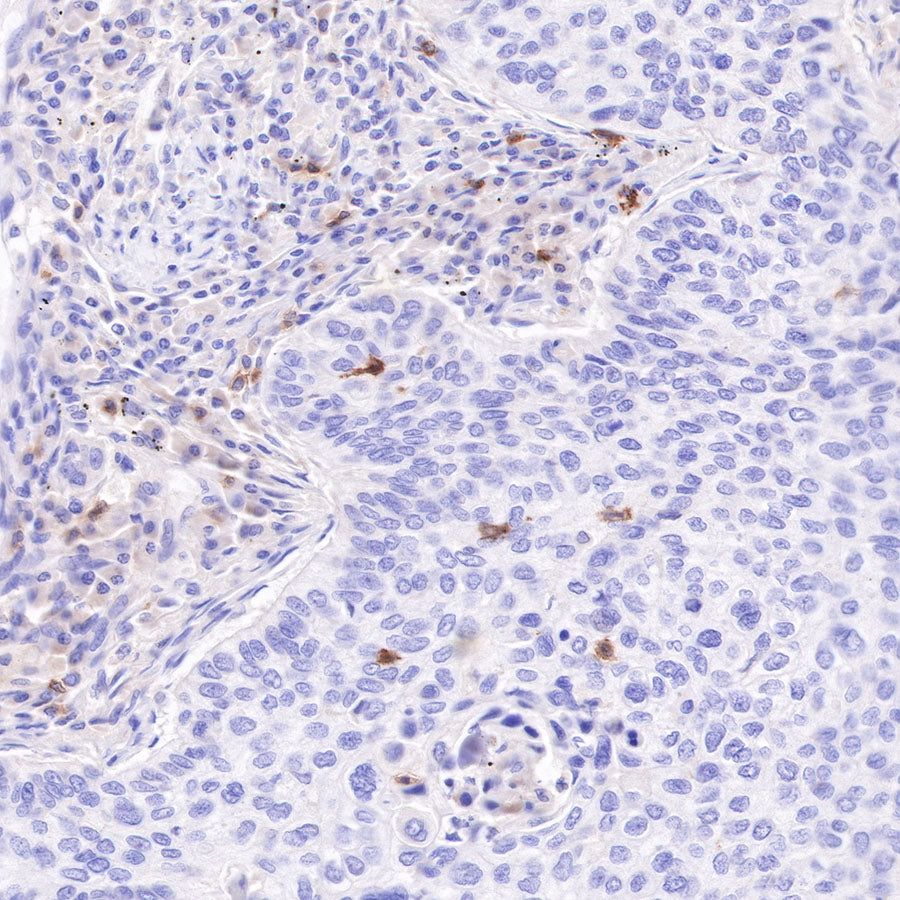

IHC shows positive staining in paraffin-embedded human pancreatic cancer. Anti-CD103 antibody was used at 1/100 dilution, followed by a HRP Polymer for Mouse & Rabbit IgG (ready to use). Counterstained with hematoxylin. Heat mediated antigen retrieval with Tris/EDTA buffer pH9.0 was performed before commencing with IHC staining protocol.